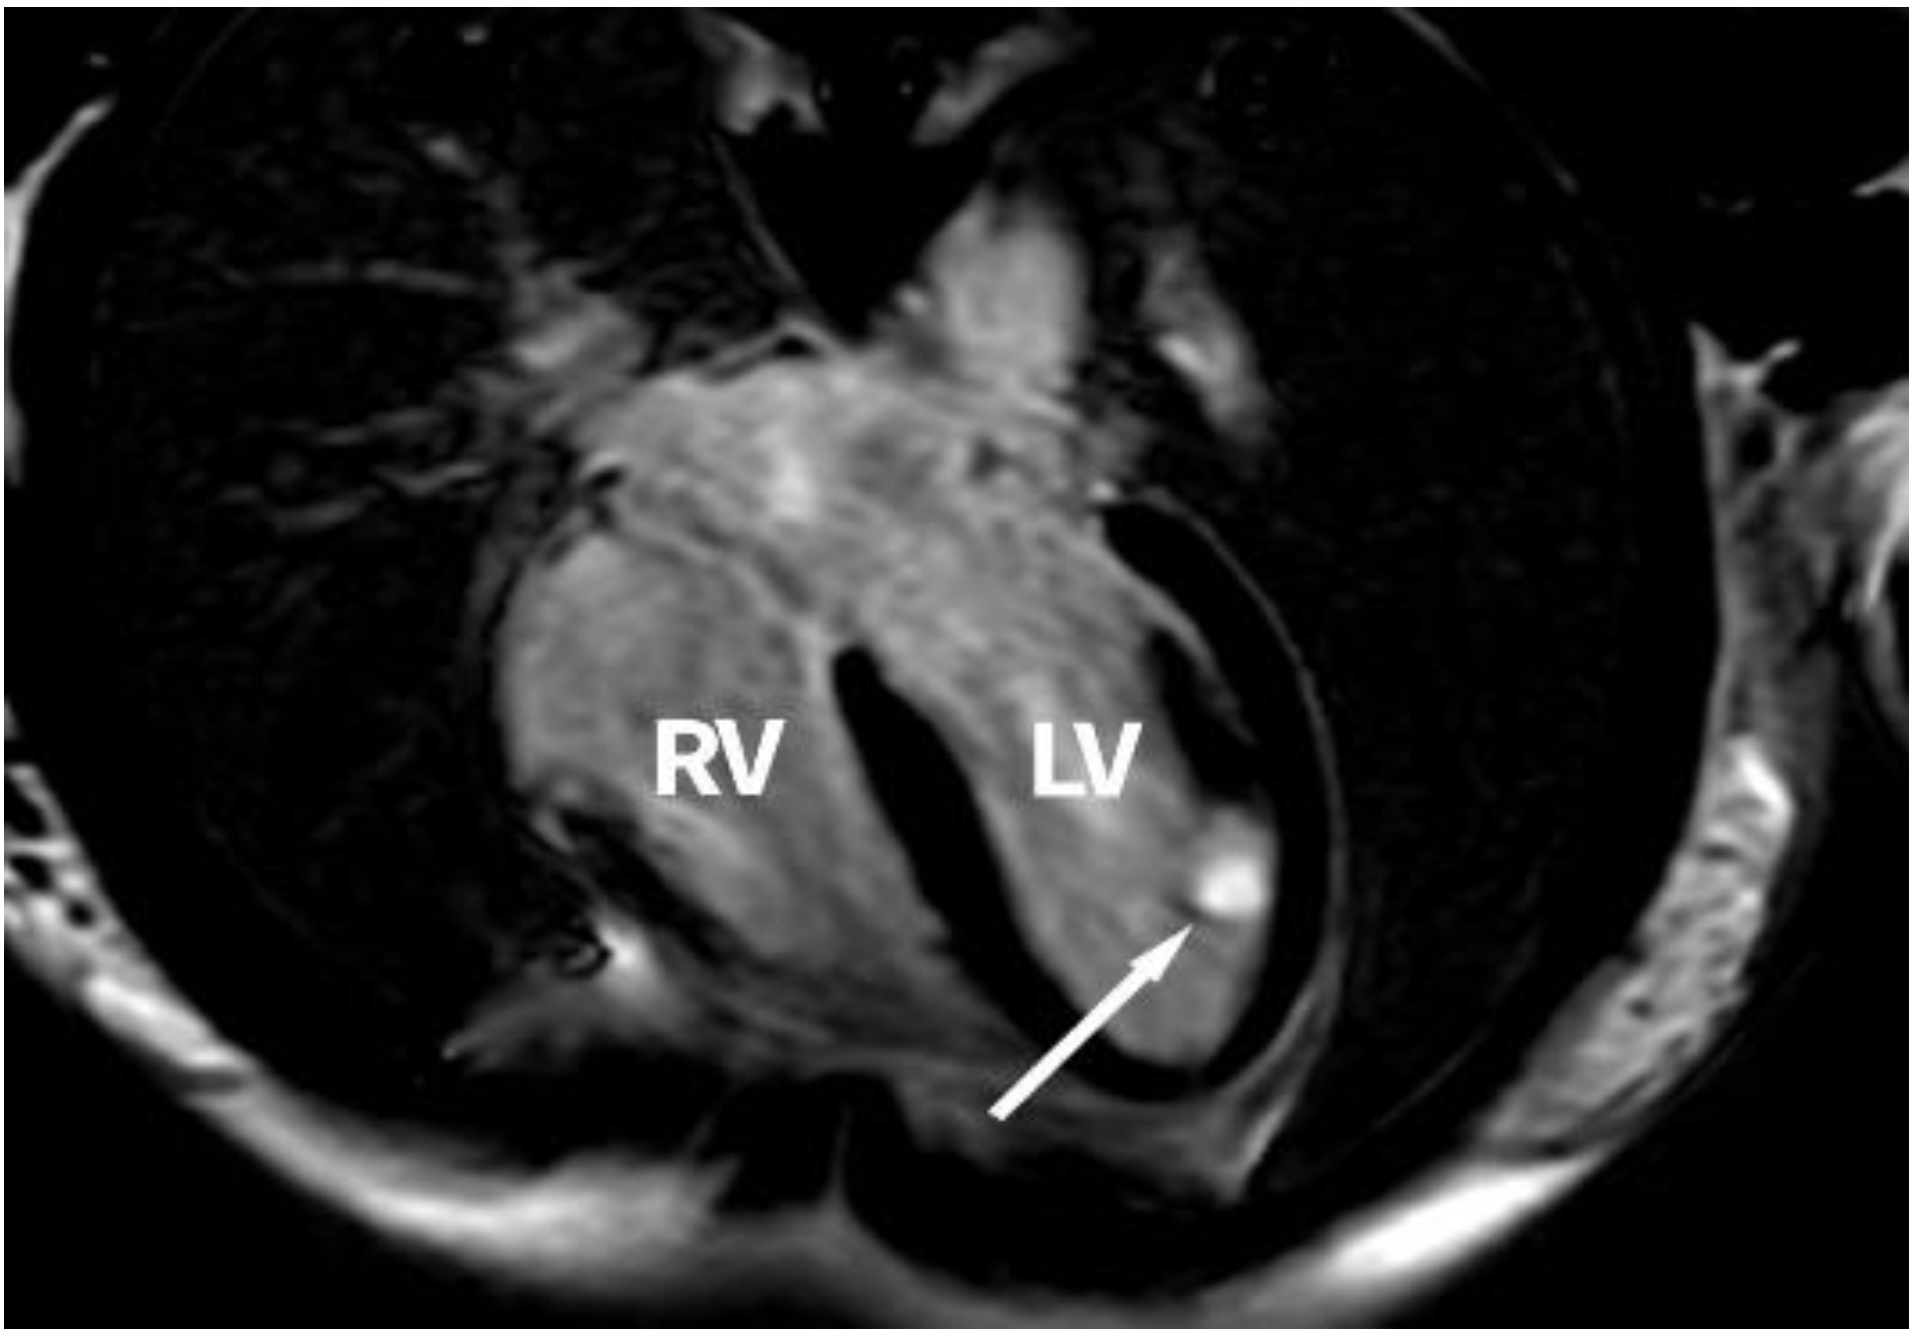

2. Case Report